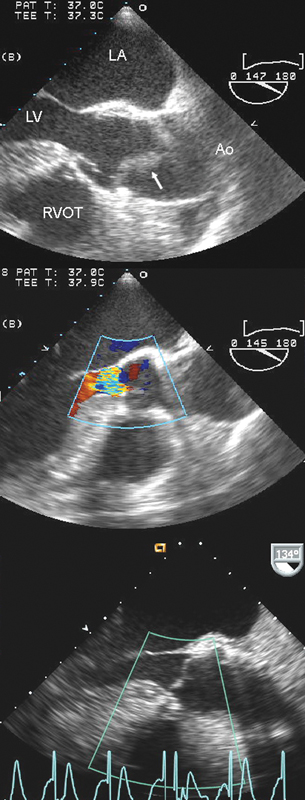

فحوصات تشخيصية لبعض امراض القلب والشرايين التاجية